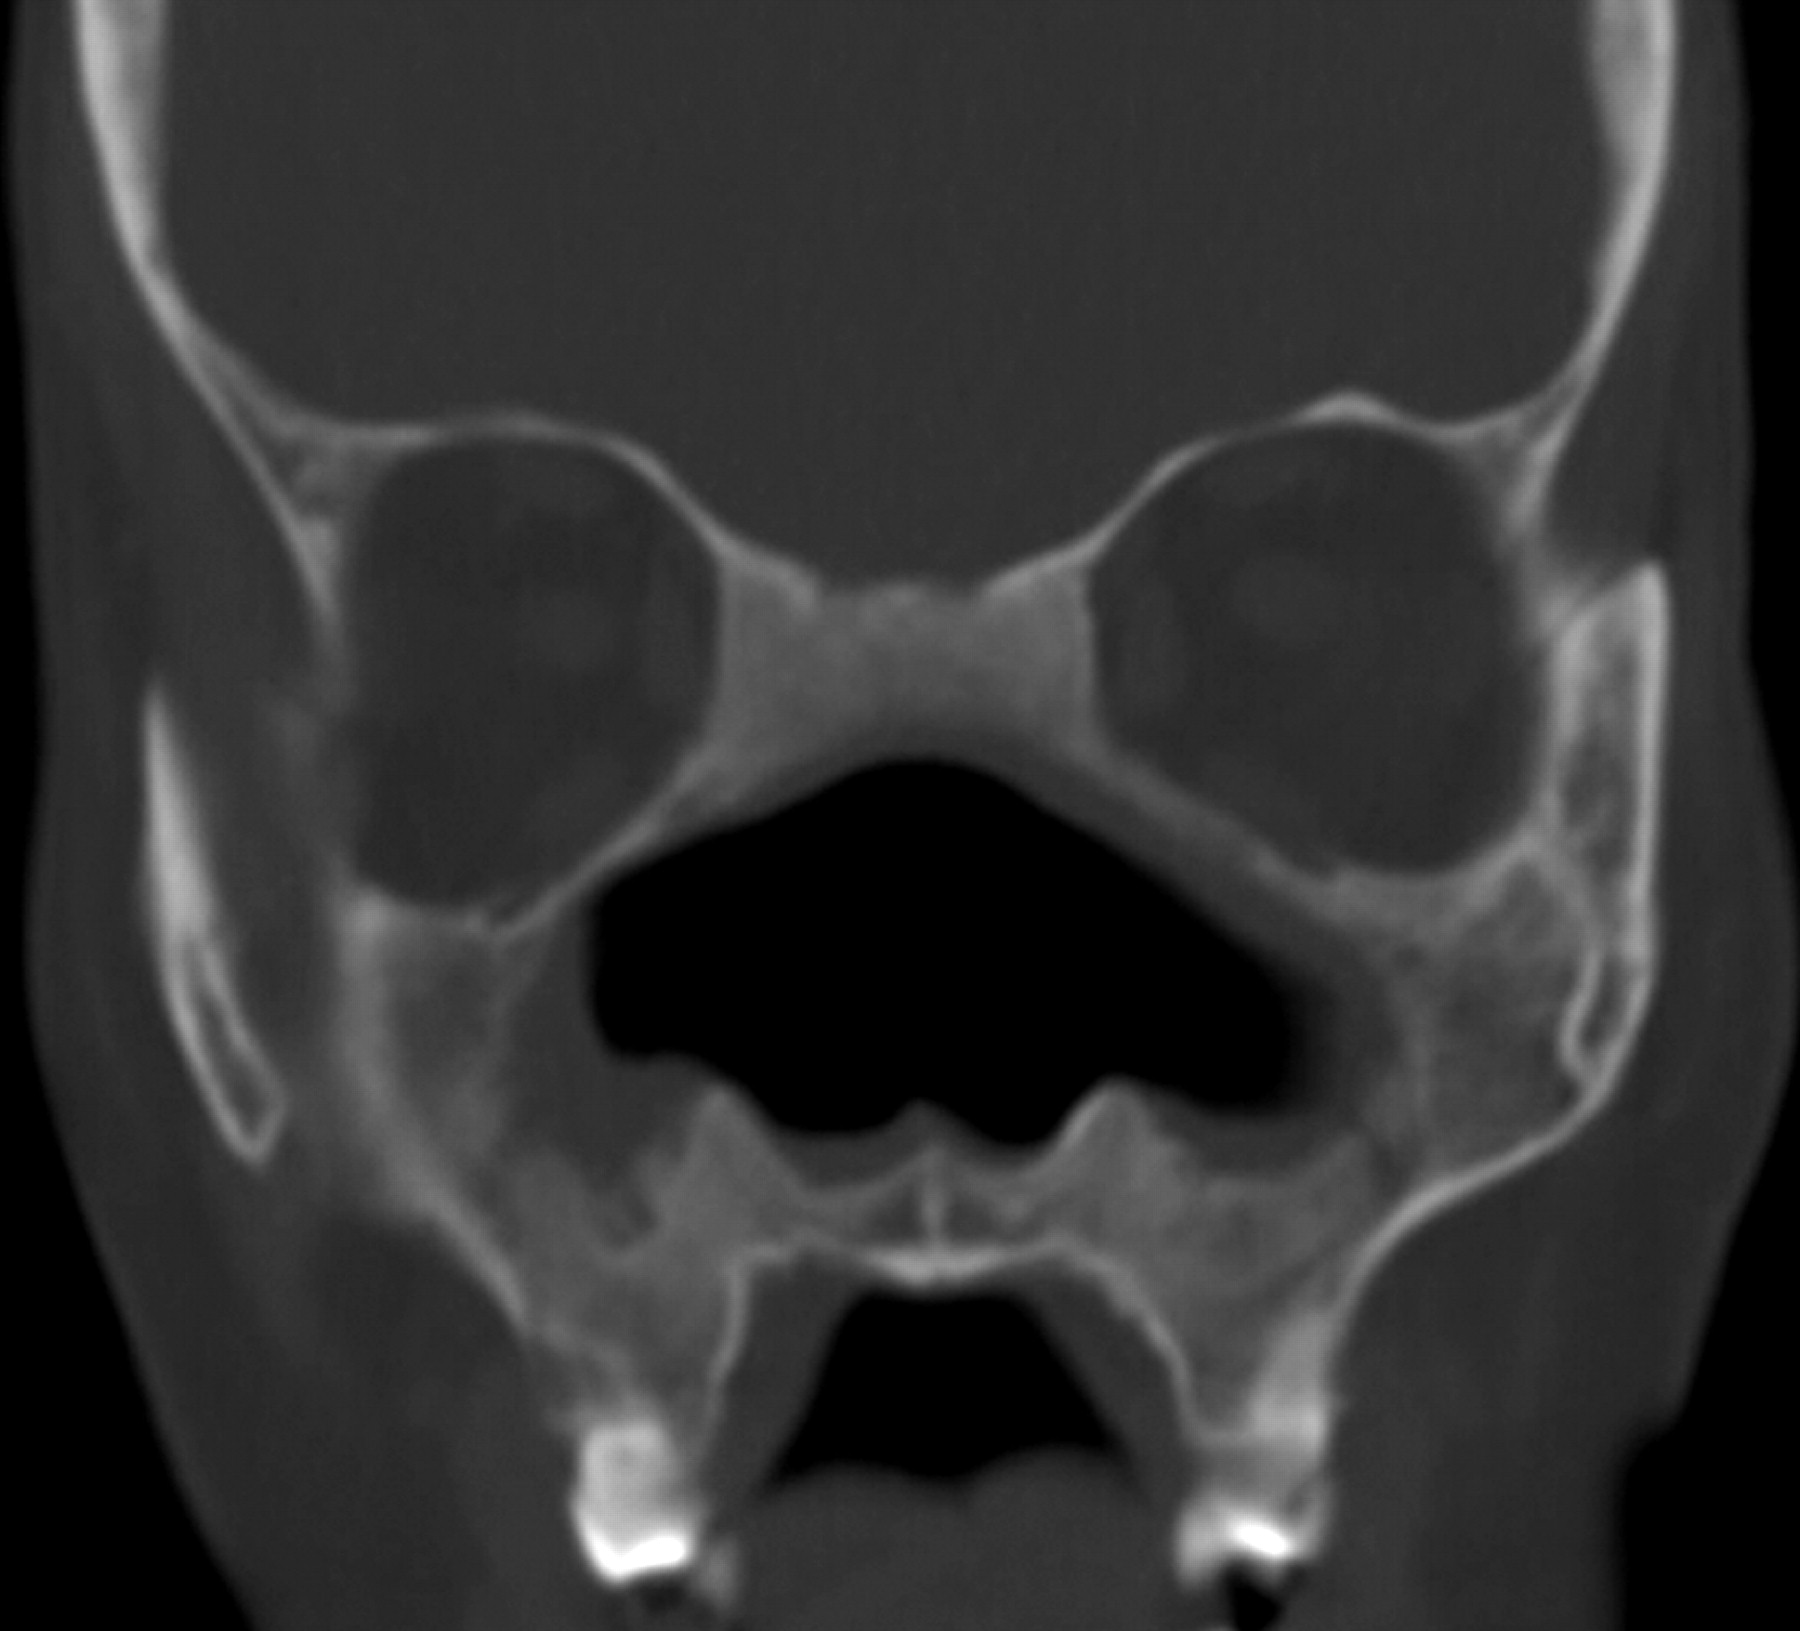

Гранулематоз Вегенера

Носовой перегородки грибковый абсцесс у новорожденного с иммунодефицитом.